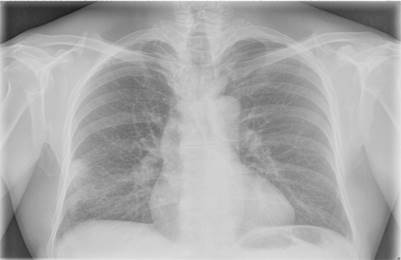

En la analítica sólo destaca una eritrosedimentación de 38 mm, proteína C reactiva en 3 mm/l y el antígeno específico prostático 0,002 ng/ml. Se indica tratamiento con amoxicilina 500 mg cada ocho horas, ambroxol un comprimido cada ocho horas e ibuprofeno 600 mg cada ocho horas durante 10 días. Al no mejorar, se realiza radiografía de tórax en la que se observa un nódulo subpleural a nivel del lóbulo medio pulmón derecho (Figura 1).